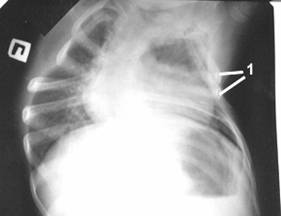

Рис. 4. Рентгенограмма грудной клетки б-ной С. 4 лет после операции.

1 - перемещенные ребра.